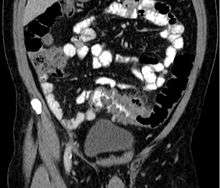

People with the above symptoms are commonly studied with computed tomography, or CT scan.[10] The CT scan is very accurate (98%) in diagnosing diverticulitis. In order to extract the most information possible about the patient's condition, thin section (5 mm) transverse images are obtained through the entire abdomen and pelvis after the patient has been administered oral and intravascular contrast. Images reveal localized colon wall thickening, with inflammation extending into the fat surrounding the colon.[11] The diagnosis of acute diverticulitis is made confidently when the involved segment contains diverticulae.[12] CT may also identify patients with more complicated diverticulitis, such as those with an associated abscess. It may even allow for radiologically guided drainage of an associated abscess, sparing a patient from immediate surgical intervention.

- ↑ CT scan of diverticulitis 2012-11-14